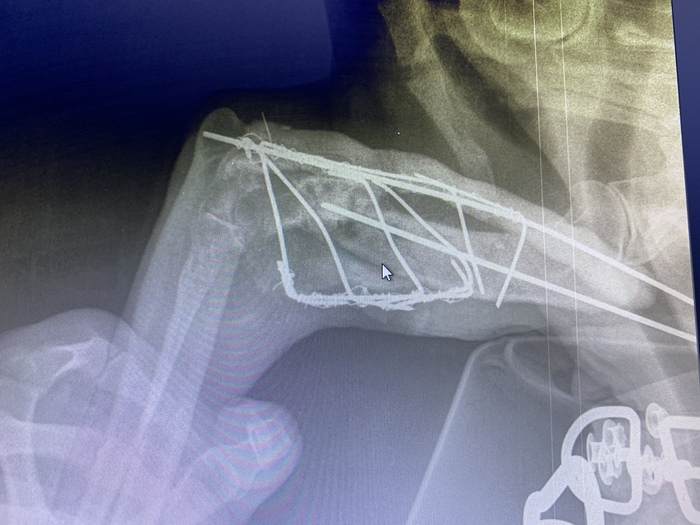

Ситуация такая. Моя собака, 8 лет, кобель, помесь английского поинтера с дворнягой, дорог мне как я сам себе (очень сильно). В результате ДТП, находясь в машине была сломана передняя левая лапа. Проведена операция ровно 30 дней назад, фиксация кости и вставлены спицы, спицы выпирают с обоих боков лапы, но публиковать фото не буду, не для слабонервных. Вопрос к ветеринарам:

1. Срастается ли лапа?

2. Как правильно давать кальций?

Судя по всему лапа не болит на данный момент, но собака на нее не наступает, болтается в каком-то странном положении, но без дискомфорта может лежать на здоровой лапе, не скулит, аппетит есть.

P.S. Для людей с возгласами про Гугл, почему не у ветеринара и тд: Единственный Ветеринар в доступности- умер, рентген сделан помощником, который не знает что делать дальше. Снимать спицы буду в другом городе, но долго ли еще будет срастаться?